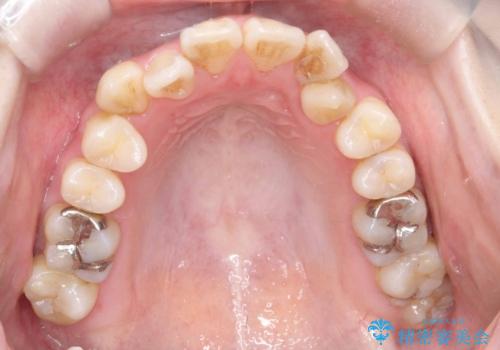

- 開咬と歯のデコボコ(叢生)、八重歯を主訴にご来院された患者様です。

矯正の精密検査の結果、上顎左右4番および下顎左右5番の計4本を抜歯し、ワイヤー矯正(クリア装置)にて治療を行いました。

虫歯があったので、虫歯治療は矯正前に行っています。

開咬や歯列のデコボコが改善され、見た目だけでなく咬み合わせの機能面も大きく向上し、大変ご満足いただけました。